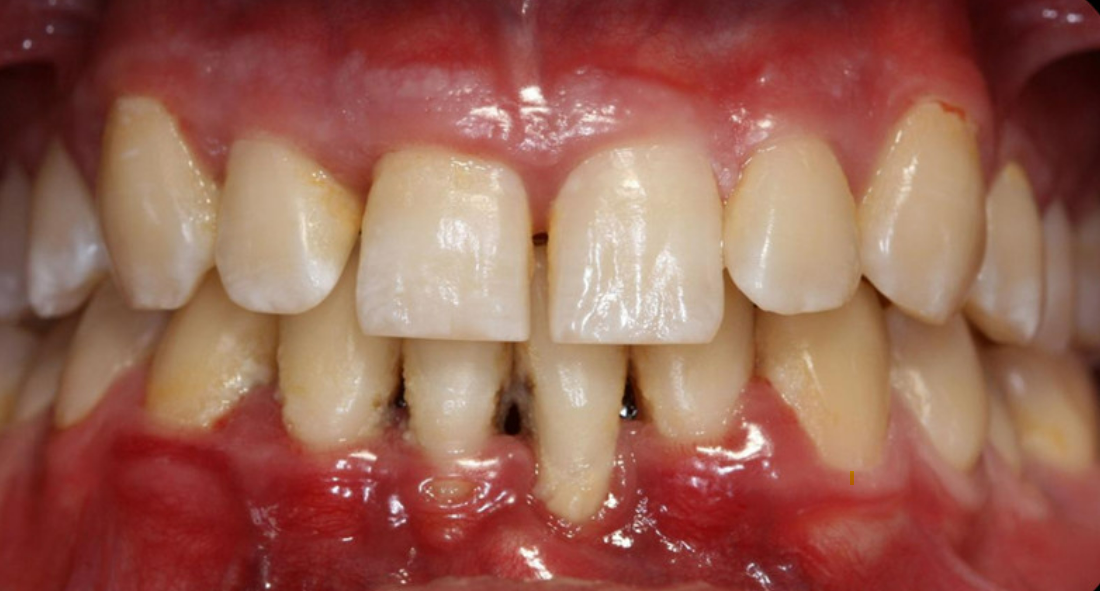

La parodontite chronique

Cette maladie chronique est caractérisée par l’inflammation des gencives pouvant aller jusqu’à la rétractation des gencives et la destruction du tissu osseux.

La parodontite agressive

La parodontite agressive: Cette maladie évolue plus rapidement que la parodontite chronique mais se caractérise par le même processus : la destruction des tissus osseux, et la perte de l’attache gingivale. Elle est très souvent dûe à des antécédents familiaux, mais concerne également plus facilement les fumeurs.

Le déchaussement des dents

Le déchaussement des dents correspond à une rétractation des gencives par rapport aux dents qui conduit à exposer les racines sous-jacentes. Différents facteurs peuvent favoriser cette maladie des dents : vieillissement, mauvaise hygiène bucco-dentaire, brossage trop vigoureux. Pour traiter le problème, le dentiste peut effectuer :